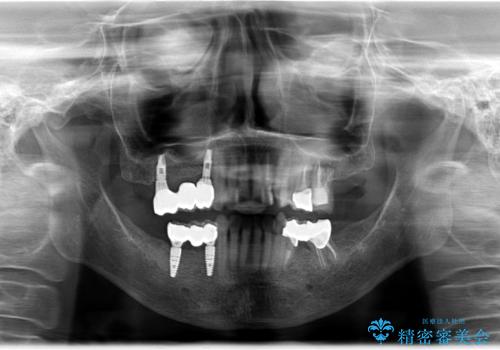

- 奥歯がとれてしまい、咬めないとのことで来院されました。

右上のかぶせ物がとれてしまい、残った根っこも虫歯になってしまっていました。

また右下の歯も虫歯と歯周病により長く使用するには難しい状態でした。

右の上下の歯を抜歯してインプラントを埋入して、かぶせ物を装着する計画としました。

右側のかみ合わせを回復するには、インプラントか入れ歯のどちらかの方法で治療する必要があました。

治療方法について十分な説明を行い、インプラント治療を選択されました。